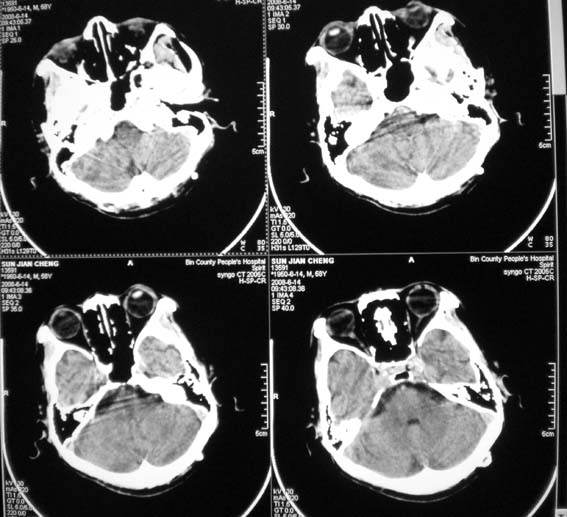

以下是引用358450m在2008-6-14 22:21:00的发言:[br]左侧外侧裂池密度增高,考虑出血。

以下是引用王仕学在2008-6-14 22:17:00的发言:[br]左侧外侧裂池密度增高,考虑出血。

以下是引用dyqct在2008-6-15 10:32:00的发言:[br]支持:1、左侧外侧裂池密度增高,考虑出血。[br] 2、左侧基底节区脑软化灶。